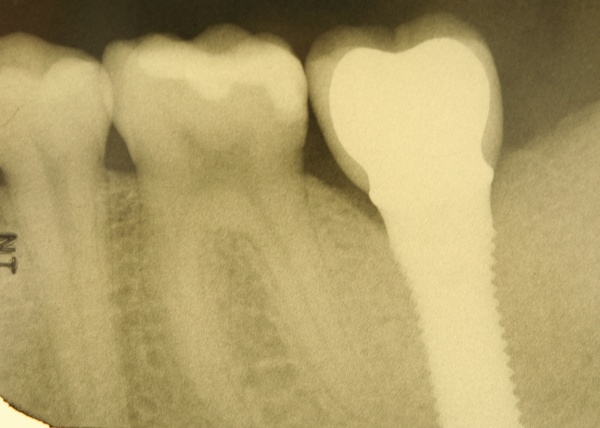

Dies lässt sich exemplarisch auch im folgenden Fall zeigen: Ein männlicher Patient mit der Diagnose einer generalisierten aggressiven Parodontitis (32 Jahre) befand sich zunächst in einer systematischen antiinfektiösen nichtchirurgischen Parodontitistherapie mit begleitender systemischer Antibiose. An der nachfolgenden unterstützenden Parodontitistherapie nahm er jahrelang teil (2007 – heute) und wies eine sehr gute Compliance auf. Im Oktober 2012 erfolgte durch mich die Implantation regio 34. Ein Jahr post implantationem zeigen sich unverändert kein periimplantärer Knochenabbau sowie klinisch gesunde Gingivaverhältnisse und physiologische Sondiertiefen (Abb. 18).